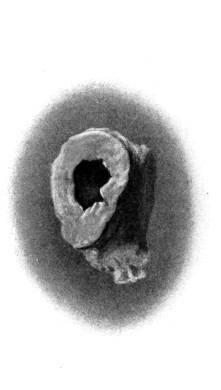

Fig. 20. An Occipital Cephalocele. (For further description, see text.)

1. Occipital cephaloceles—the commonest variety—occupy, anatomically, two positions (1) between the two lower segments of the occipital bone (inferior occipital cephaloceles), often involving the foramen magnum and sometimes complicated by a condition of cervical spina bifida, and (2) between the two upper segments of the occipital bone (superior occipital cephaloceles), occasionally involving the posterior fontanelle.

Sincipital cephaloceles are usually quite small, but the occipital variety and those situated in[35] the region of the anterior fontanelle frequently attain a great size (see Figs. 20-22).

Fig. 22. An Occipital Cephalocele. (For further description, see text.)